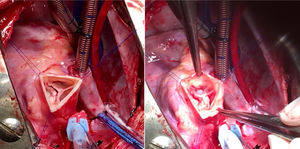

El futuro de la cirugía de reparación valvular múltiple en los pacientes con cardiopatía congénita es incierto. Hay debate sobre el material y las técnicas a emplear. Idealmente no hay que emplear material protésico que degenera con el tiempo y no crece, e intentar trabajar con el tejido autógeno siempre que sea posible. En nuestro caso, ha sido frecuente emplear varias técnicas distintas para reparar una misma válvula5,6,12,14. Este tipo de reparaciones difiere de los cánones habituales de la reparación de valvulopatías adquiridas. En el caso de los defectos de los cojinetes endocárdicos, habitualmente no empleamos anillos protésicos para la válvula mitral. Los defectos de este estilo se corrigen bien cerrando el cleft mitral y a veces es preciso asociar una comisuroplastia. La arquitectura de las válvulas auriculoventriculares de estos pacientes está alterada, y comparado con la anatomía habitual, un anillo protésico distorsiona la plastia mitral15,16. El abordaje cambia cuando la etiología de la valvulopatía mitral es una displasia primaria no asociada a defecto del septo auriculoventricular; aquí la reparación es más compleja, requiriendo diversas técnicas para conseguir una buena coaptación de los velos. En este tipo de pacientes sí es necesario asociar un anillo mitral para consolidar la reparación, siempre y cuando el tamaño del paciente nos lo permita (fig. 2). En la válvula tricúspide se emplea más libremente el anillo o, en su defecto, una plastia de Vega cuando el paciente es pediátrico. En el caso de la válvula aórtica recomendamos afeitado de velos y apertura de comisuras en válvulas estenóticas para ganar movilidad, aunque el arsenal terapéutico para anillos pequeños es más limitado (fig. 3). En los casos de insuficiencia aórtica se hará plastia de velos para evitar que estos prolapsen y logren una buena altura de coaptación, y si esta se asocia a dilatación aneurismática de la raíz aórtica se realizará técnica de David. Cuando la valvuloplastia convencional no es suficiente hay que explantar la válvula, teniendo como principal opción el Ross en lactantes y niños pequeños. Nuestra experiencia inicial con la técnica de Ozaki (reconstrucción de neovelos aórticos) es buena y puede tener un papel en los candidatos que requieran la reparación de 2 o más válvulas13.